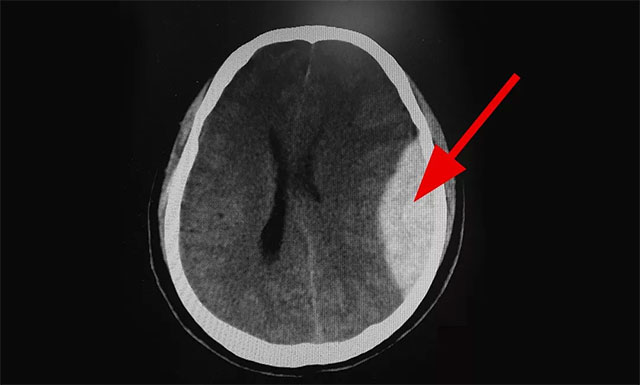

▲ 患者出血严重,情况危急

10:01,CT检查结果显示:患者为左侧额顶叶急性硬脑膜外血肿伴脑疝形成,病情非常危急,卒中小组立即联系脑血管病区主任张琪博士,随后完善各项检查,待手术准备就绪,行左侧额顶叶急性硬脑膜外血肿清除术。